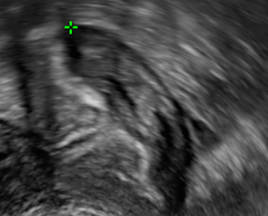

Unauffällige oviarielle Reserve, AFC 8

Reduzierte ovarielle Reserve, AFC 2

AFC erhöht bei PCOS, ACF > 15